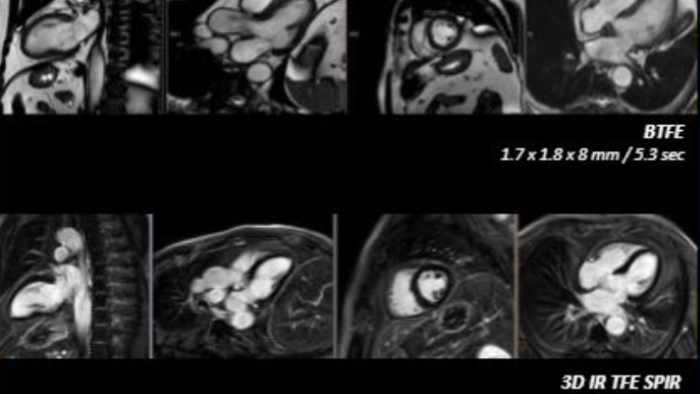

You can still access recordings of 4 full days of hands-on workshops about best practices in multimodality cardiac imaging with expert teams. See first-time-right imaging for cardiac care, including valvular and related diseases, cardiomyopathies, and intracardiac masses and cardiac tumors.

If you were registered for ESC 2023, but were not able to attend the satellite symposium, you can still view it through the ESC website. Top cardiology thought leaders addressed some of the major challenges in peri-interventional and diagnostic echocardiography, such as advancing and complementing imaging techniques during tricuspid valve interventions, a revolutionary imaging workflow for occlusion of the left atrial appendage, and the importance of first-time-right ultrasound imaging during cancer therapy.